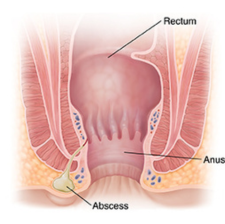

Perianal Abscess

A perianal abscess is a type of anorectal abscess that is confined to the perianal space.Other causes can include inflammatory bowel diseases such as Crohn's disease, as well as trauma, or cancerous origins. Patients with recurrent or complex abscesses should be evaluated for Crohn's.

Rectal Abscess

A collection of pus in the tissue around the anus and rectum.Anorectal abscess is usually caused by anal infection or blocked glands. It can result from sexual transmission or a disorder, such as Crohn's disease or